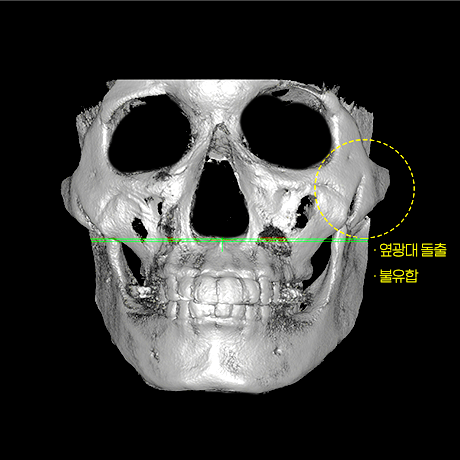

하이엘 절골 진행하여

45° 광대 축소

좌우 비대칭 개선

옆 광대 불유합 개선